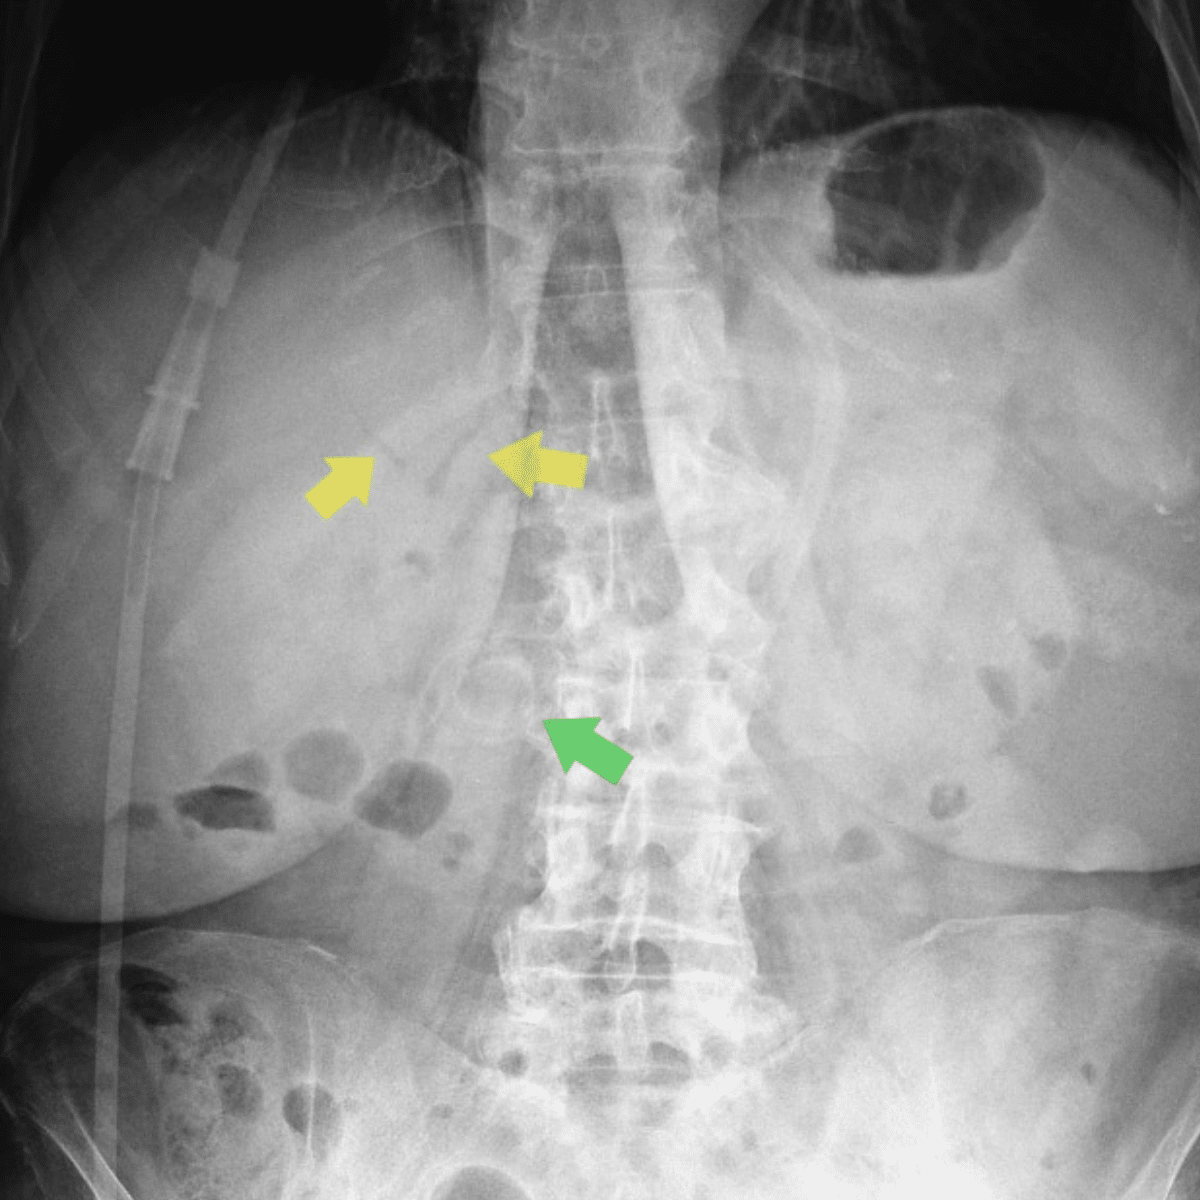

Case 2: Bouveret syndrome with Rigler’s triad: air within the gallbladder (blue arrow), cholecystoenteric fistula (red arrow) with ectopic gallstone in proximal duodenum, and gastric distention (yellow arrow). Radiopaedia